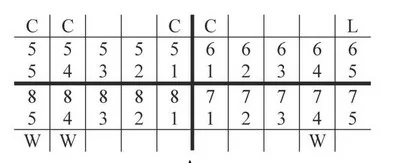

Instrumentem przedstawionym na ilustracji stosowanym w chirurgii stomatologicznej jest

| 1 | 1 | 1 |

| 17-14 | 13-23 | 24-27 |

| 47-44 | 43-33 | 34-37 |

| 1 | 3 | 1 |